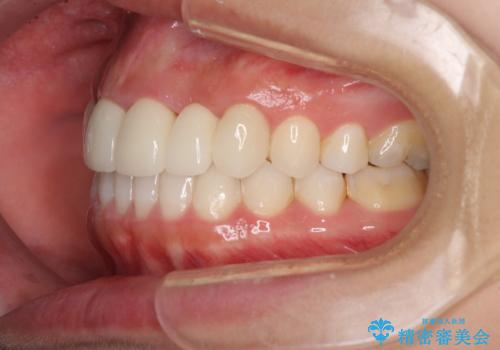

矯正治療により下顎前歯を整列させたため、上顎前歯のセラミックブリッジを補綴することで口元を少し下げることができました。

ヒトの目線がいつも口元に向けられているように感じることがなくなり、患者様には大変満足していただきました。